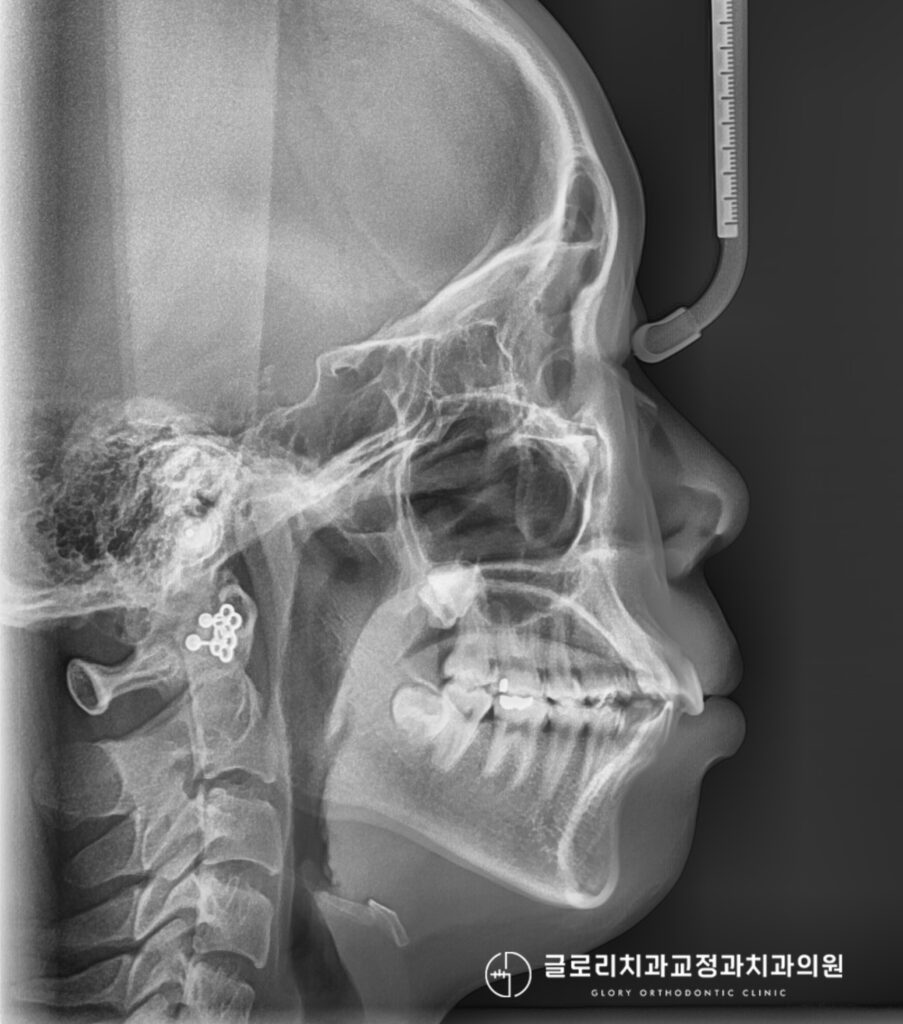

골격성 2급 부정교합?

구강 내 사진을 보면 현재 위아래 치아가 전체적으로 고르지 못하게

배열되어있으며 특히나 왼쪽 위 송곳니는 정상적인 위치에서 벗어나

바깥쪽으로 맹출되어있는 모습을 확인할 수 있습니다.

또한 현재 윗니가 아랫니를 과도하게 덮고 있는 과개교합이 동반되었습니다.

그로 인해 전반적으로 구강의 돌출감이 관찰되죠.

현재 관찰되는 골격성 2급부정교합을 해결하기 위한 교정이 필요할 것으로 보여집니다.